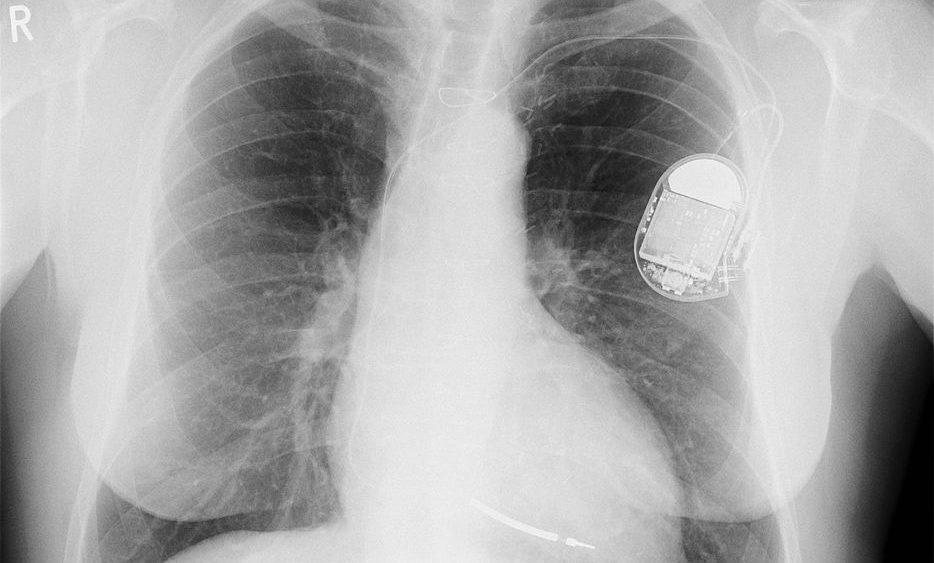

Dispositifs médicaux pacemaker

Les journalistes ayant participé à l’enquête Implant Files, révèlent des problèmes concernant du matériel comme, par exemple, des pacemakers, des pompes à insuline, des prothèses mammaires ou de la hanche… Ainsi, de nombreux dispositifs médicaux implantés dans le corps ne sont pas assez contrôlés et ont une traçabilité insuffisante.